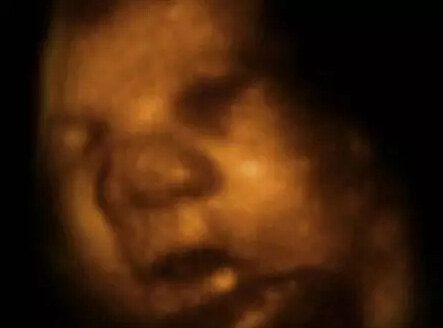

从4-D扫描图的特写镜头可以看到,这个差不多足月的胎儿在吸食羊水。这有助于胎儿为迎接子宫外的生活锻炼消化系统。

研究中运用了4-D扫描图像,这些图像通过真实拍摄的3-D扫描图像合成。

这部名为《子宫里:双胞胎、三胞胎和四胞胎》的纪录片,通过计算机生成图像,将真实扫描数据制作成令人叹为观止的画面。

看到他们脸部表情的细节,比如微笑和眨眼,还有多胞胎之间的互动,都让我感到非常震惊。“